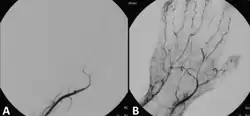

![]() Angiograph before and after thrombolytic therapy in a case of acute limb ischemia. | |